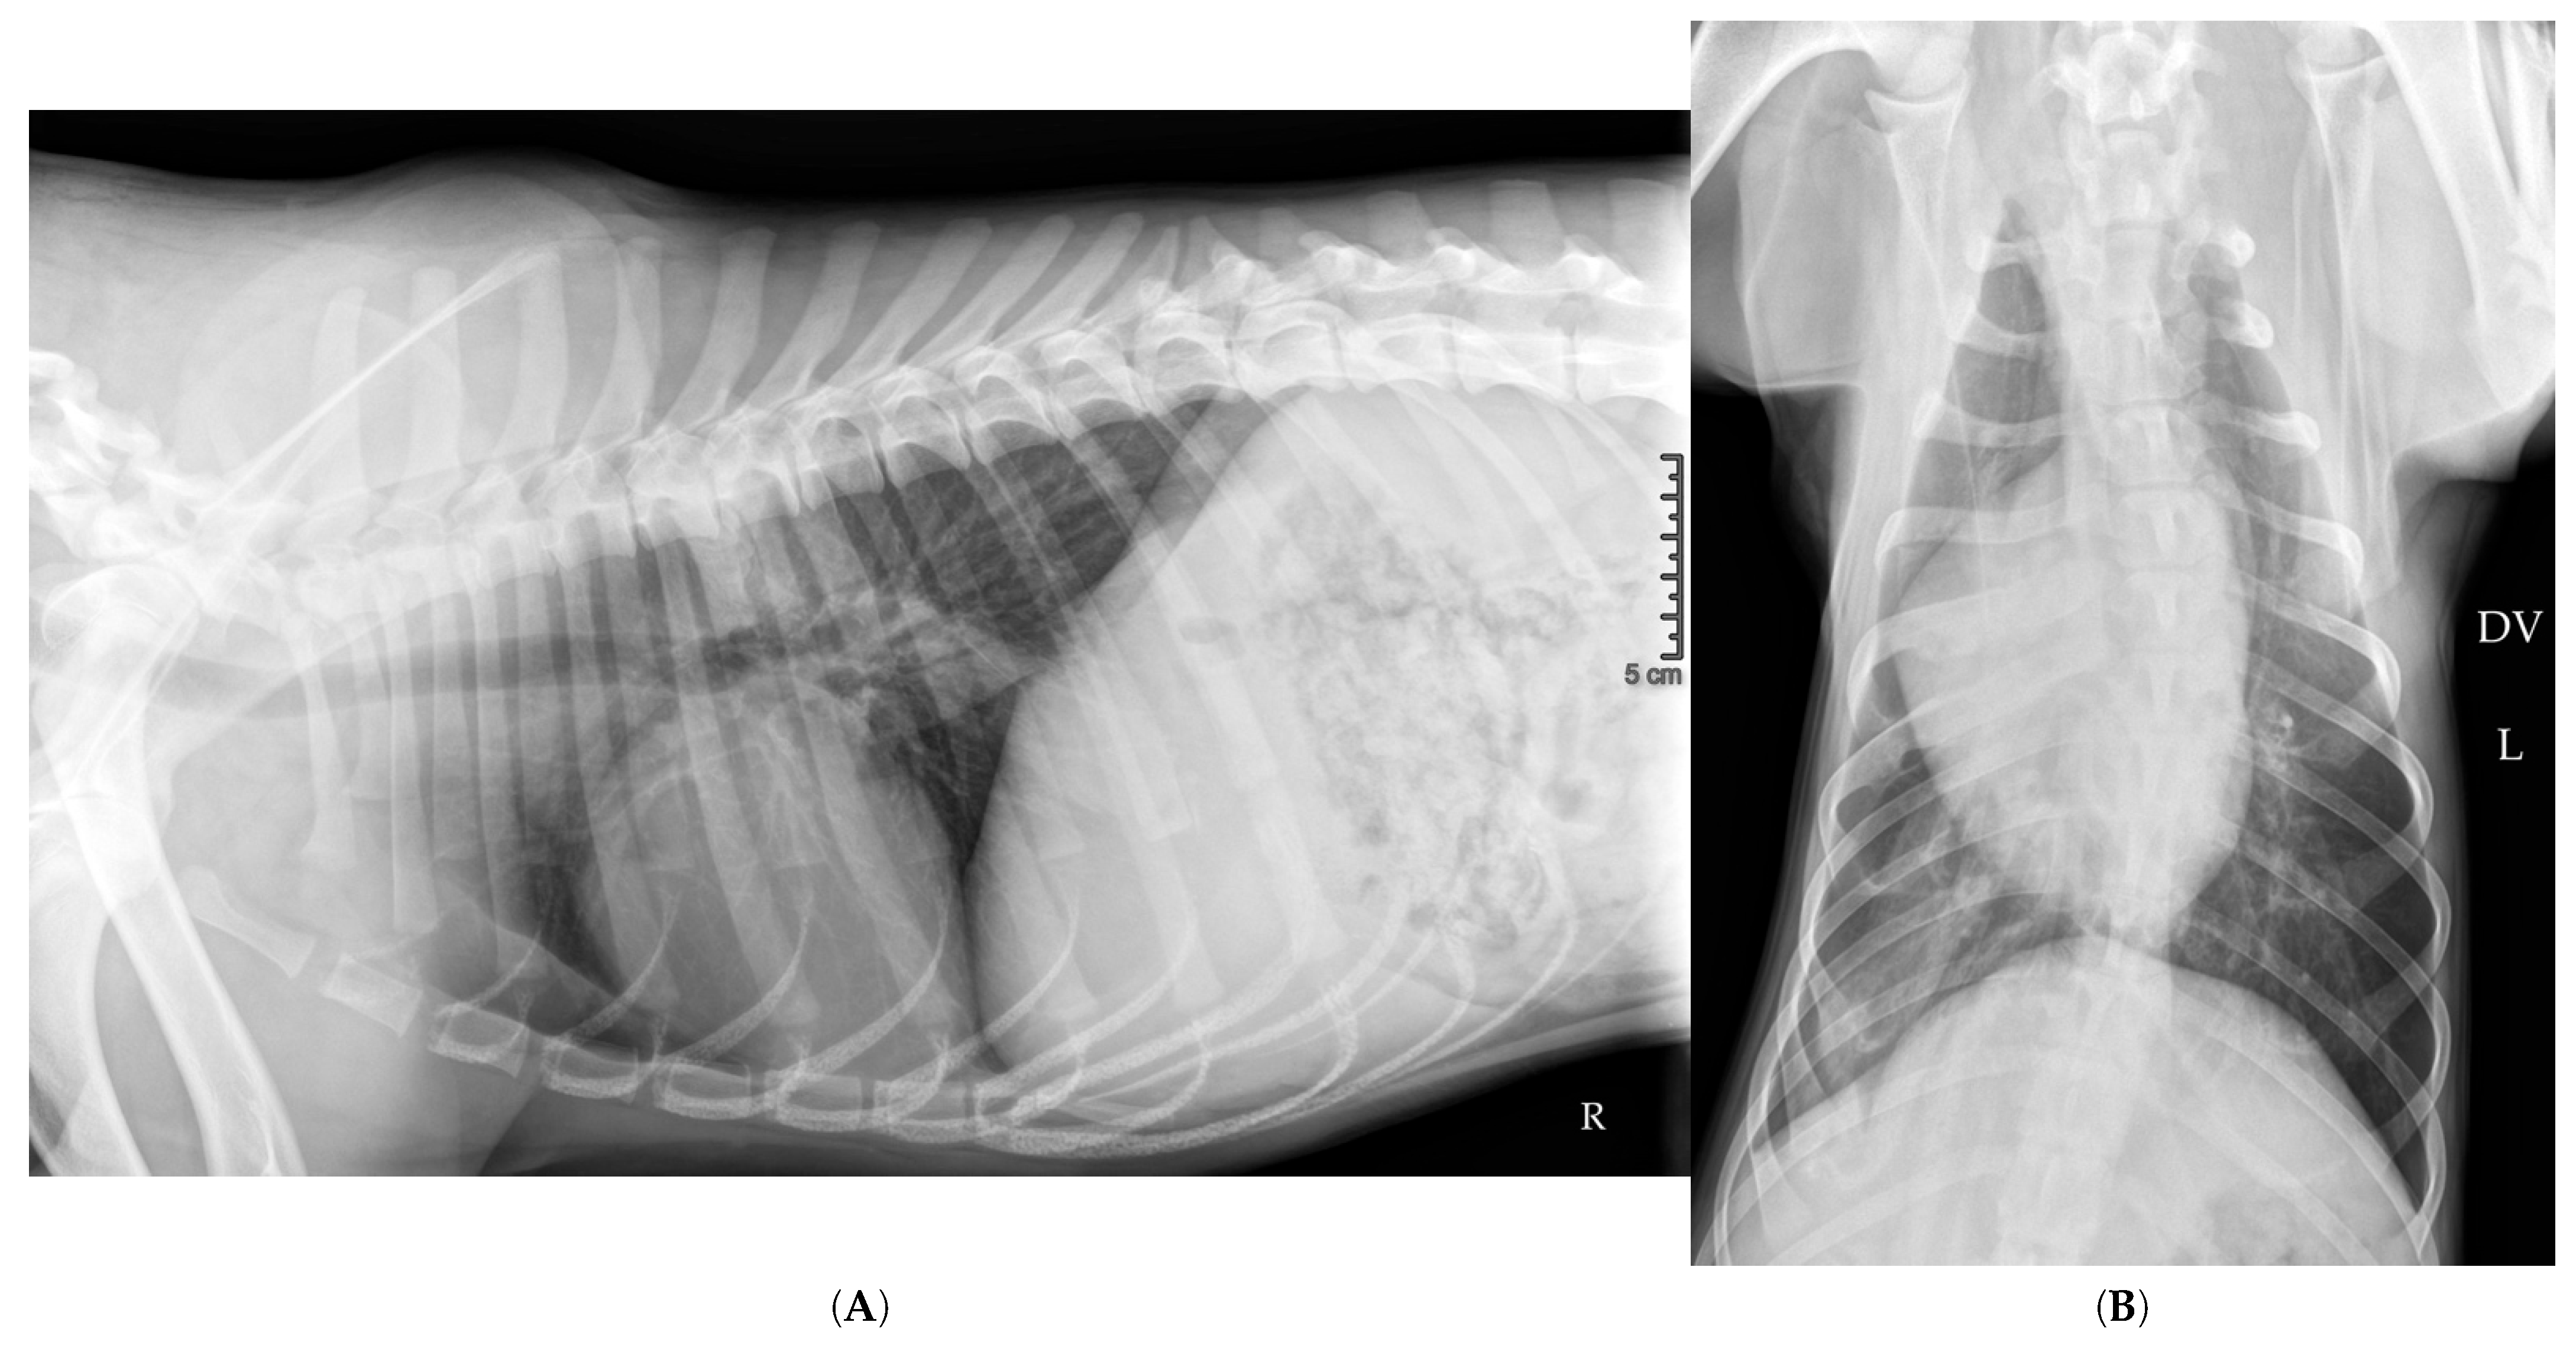

2.10. Hospitalization Follow-Up

3.4.5. Re-Expansion Edema?